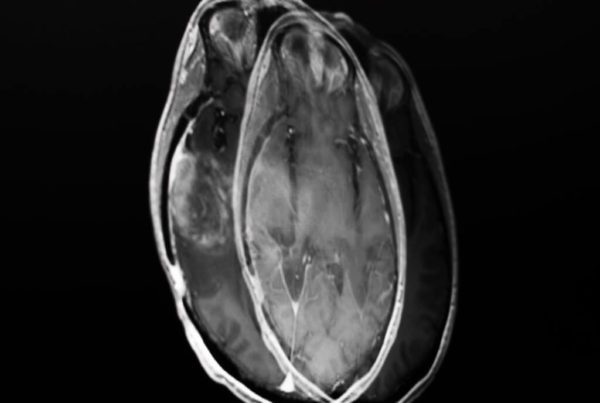

DICOM is not just an image format — it’s a complete clinical data representation system. Every DICOM file carries not only image pixels but a rich set of structured metadata describing the patient, study, series, equipment, and acquisition conditions.

For those accustomed to formats like JPEG or PNG, the difference is staggering. While those formats store only visual data, a DICOM file is essentially a database embedded within the image itself. Every piece of information is organized through tags — numeric identifiers following the (GGGG,EEEE) format, where GGGG is the group and EEEE is the element.